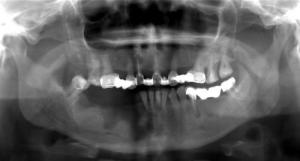

Этот процесс может обостряться. В таком случае ребенок жалуется на болезненные ощущения в челюстной области и припухлость. Появляются свищи. В окружающих тканях может образоваться абсцесс и флегмона. В период ремиссии немного увеличены регионарные лимфоузлы. Они становятся менее подвижными и болезненными при пальпации. Могут погибнуть значительные костные участки. Зоны активного челюстного роста могут повредиться. У третей части пациентов происходит секвестрация, а также патологические переломы отростка мыщелка. Впоследствии это приводит к деформации системы зубов и челюсти. Обычно такие осложнения наблюдаются до семилетнего возраста.

Рентгенологическое исследование является главным методом, который позволяет определить протяженность и локализацию пораженного очага. С помощью рентгена можно установить патологоанатомические изменения. Большую ценность представляет и томография. Всем пациентам, у которых выявлена свищевая форма заболевания, делают фистулографию. Этот метод основан на введении рентгеноконтрастного вещества в пораженную костную полость через свищевой ход. Затем выполняется рентгенография в двух проекциях. Точная пораженная зона определяется с помощью радиоактивного сканирования, при котором применяется радиоактивный технеций. С помощью этого можно решить вопрос об операции.

Для продуктивной формы характерно отсутствие секвестров и увеличение костной ткани в зоне воспаления. Встречается только при остеомиелите нижней челюсти.

Хронический остеомиелит на рентгенограммах проявляется гиперостозом (и, как следствие, деформацией кости), очагами деструкции кости, окружёнными зоной склероза, секвестрами, остеопорозом. Фистулографию используют для диагностики свищей между полостями деструкции и мягкими тканями.